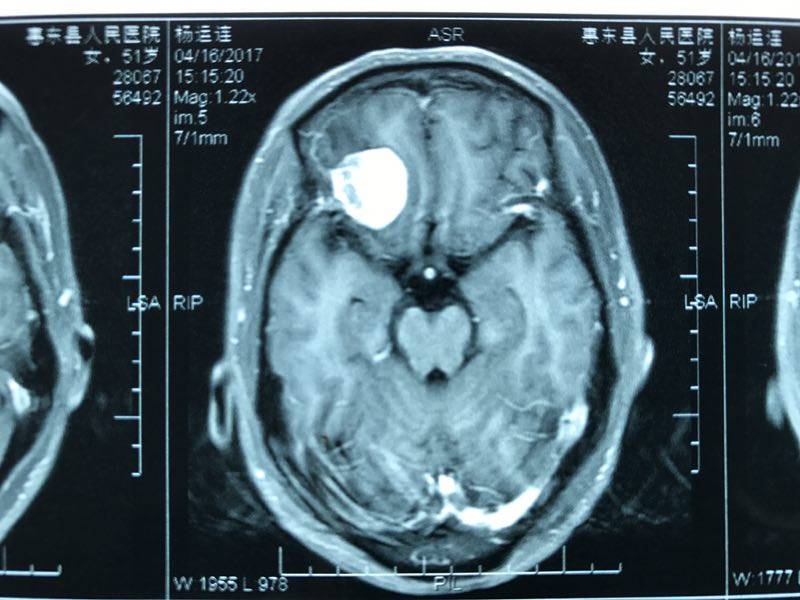

當(dāng)時(shí),它住在一位52歲阿姨的腦子里,本來(lái)和平共處,相安無(wú)事。有一天不小心喝多了吃撐了,一下子胖了不少,將正常的腦組織擠了一下,阿姨頓時(shí)就抗議了,暈得天旋地轉(zhuǎn),嘔吐不止,還觸發(fā)了她的冠心病,出現(xiàn)了胸悶、心悸的癥狀。正當(dāng)腦膜瘤為自己的“蝴蝶效應(yīng)”洋洋得意時(shí),阿姨被送到了惠州市第三人民醫(yī)院神經(jīng)外科,一個(gè)頭顱CT便初步將它鎖定。

3D打印技術(shù)下,醫(yī)生發(fā)現(xiàn)該腫瘤位于前顱底,經(jīng)過(guò)綜合考量及討論,最終決定采取微鎖孔手術(shù)入路,為病人設(shè)計(jì)了一例個(gè)性化的手術(shù),全稱(chēng) “右側(cè)經(jīng)眉弓鎖孔前顱底腫瘤切除術(shù)”。

以上為術(shù)前腦膜瘤不同切面pose照(冠狀位、矢狀位、軸位)